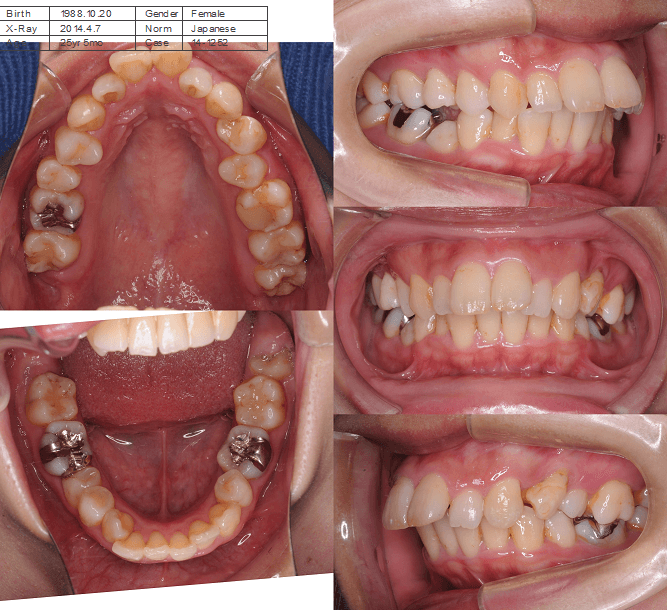

前歯の歯並びの乱れ(叢生)が気になる

| 年齢・性別 | 25歳女性 |

|---|---|

| 主訴 | 前歯の歯並びの乱れ(叢生)を気にされて来院された。咬み合わせや審美的な改善を希望されていました。 |

| 治療期間・回数 | 4年5ヶ月・30回 |

| 費用 | 1100,000円(税別) |